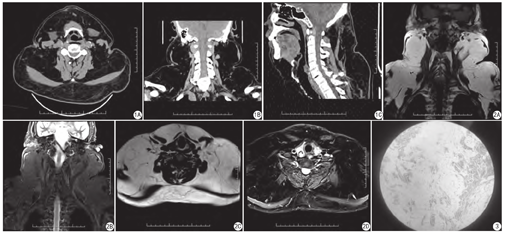

CT全颈部(软组织)平扫示双侧枕部头皮下,前、后、侧颈部皮下及肌间隙内见多发对称性脂肪密度影,无明显边界,无包裹。颈部MRI示双侧枕、颈部皮下脂肪层明显增厚,呈多发对称性,信号呈短T1、长T2信号,压脂T2呈低信号,无明显边界(图1,图2)。

患者俯卧位,在全身麻醉状态下行枕颈后皮下脂肪瘤切除术,并将切除肿瘤送检(图3)。